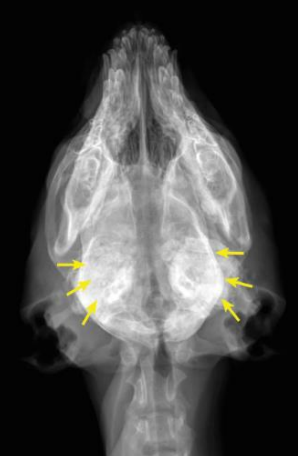

![]() ![]() | - caudal mandibles의 irrecular bone density가 증가. - tympanic bullae의 밀도도 증가. - 1/3의 환자는 mandible에 국한된 병변을 보이지만, 일부 경우 skull의 바닥에 병변, 또는 두개골 자체가 비대(thickened calvarium). - 개가 성숙해 가면서, 새로운 뼈의 가장자리가 매끄러워지고, 비정상 부위가 줄어듦. |

![]() | - tympanic bullae가 안 보일 정도로 두꺼워져 있음. |